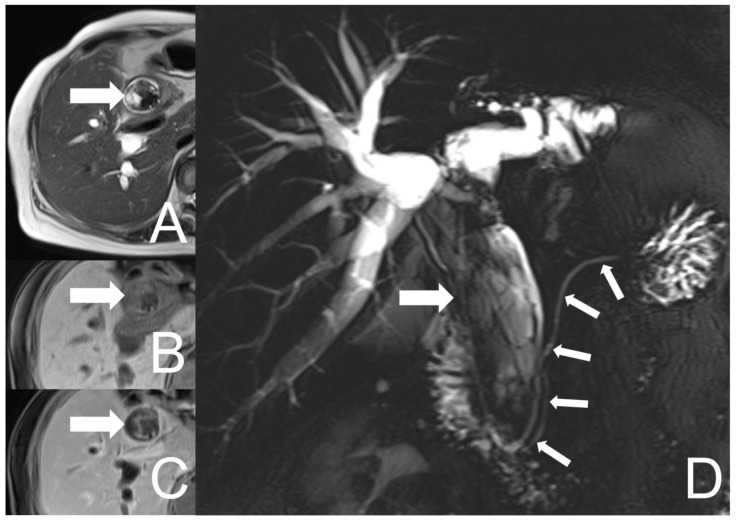

Unfortunately, the patient experienced right epigastric pain, jaundice and low-grade fever 10 months after her first presentation. Elevated levels of alkaline phosphatase (403 U/L), total bilirubin (2.1 mg/dL), direct bilirubin (1.36 mg/dL) and CA 19-9 (10.94 Unit/mL) were noted. Aspartate aminotransferase (38 U/L), alanine aminotransferase (43 U/L), CEA (2.05 ng/mL) and AFP (2.19 ng/mL) were within normal ranges. The abdominal CT and MRCP were undertaken which showed similar findings as prior images, but a progression in biliary tract dilation and an enlarged lesion size (about 11.3 cm × 3.2 cm), with more conspicuous cystic parts and heterogeneous enhancement (Figure 3). Neither enlargement of the regional lymph nodes nor invasion to the adjacent tissue were found.

The imaging features of UCOGC have not been well described due to the rarity of this entity. Few case reports and series have been reported mainly focusing on pancreatic UCOGC, in which a larger tumor size containing a cystic component was noticed compared with conventional pancreatic ductal adenocarcinoma [ref. 20]. Additionally, dilatation of the bile duct and pancreatic duct along with the presence of necrotic areas were commonly observed [ref. 21,ref. 22]. Occasional calcification, hemorrhage and venous tumor thrombus had also been recorded [ref. 23,ref. 24]. On magnetic resonance imaging (MRI), UCOGC usually presented a well-defined hypovascular lesion with low signal intensity on T1- and T2-weighted images, probably resulting from hemosiderin deposits, and relatively high signal intensity in the central area, probably reflecting the necrotic part of it [ref. 25]. Despite its large volume and rapid tumor growth, tissue infiltration and lymph node metastases were not common, with relatively low malignancy and late clinical symptoms [ref. 26]. In a case report of UCOGC of the distal CBD, a polypoid well circumscribed, cystic, rapid growing mass with hemorrhage in the ductal lumen was depicted [ref. 15]. In keeping with their findings, our case showed a huge (9.8 cm × 1.9 cm) lobulated, relatively well-defined hemorrhagic mass in the dilated CHD and CBD, with heterogeneous enhancement. On the follow-up images, it revealed rapid growth (11.3 cm × 3.2 cm 9 month later) with more prominent cystic parts and dilatation of the biliary tract. Neither definite evidence of invasion to the adjacent tissue nor enlargement of the regional lymph nodes were discovered, which was consistent with the features of this entity described in prior literatures.